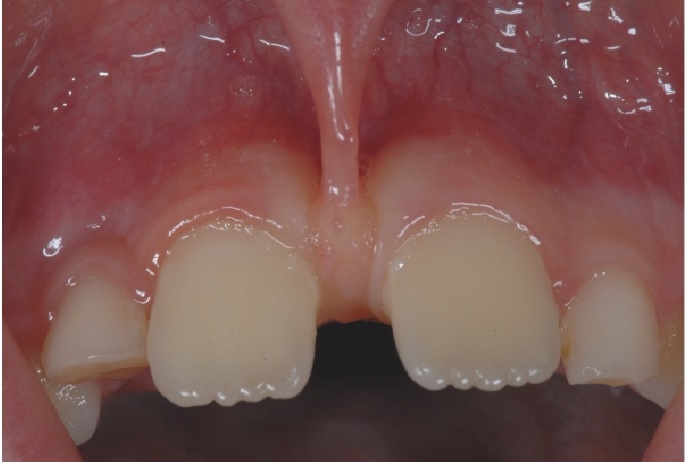

Frenulum (yüyən), diş əti toxuması (gingiva) ilə dil, dodaq və yanaq arasında yerləşən, toxumaları bir-birnə bağlayaraq hərəkətlərini sərhədləndirən yumuşaq selikli qişa toxumasıdır. Frenulum normal ölçülərdən böyük və qalın olduqda və ya diş əti kənarına yaxın yerləşdikdə bəzi narahatlıqlara və məhdudiyyətlətə səbəb ola bilir. Diş əti çəkilməsi, estetik məhdudiyyət, diastema, çıxan protez istifadə edən şəxslərdə protez fiksasiyasının məhdudlaşması və s. durumlar bununla bağlı ola bilir.

Sadalanan məhdudiyyətlərin ortadan qaldırılması və ya önünə keçilməsi məqsədilə frenulumun tamamən uzaqlaşdırılması (frenektomiya) həyata keçirilir. Bu prosedur həm ənənəvi cərrahi həm də lazer cərrahiyyəsi metodu ilə aparılır. Hansı metodun tətbiq edilməsi hər bir kliniki halda fərdi şəkildə qərara alınır.